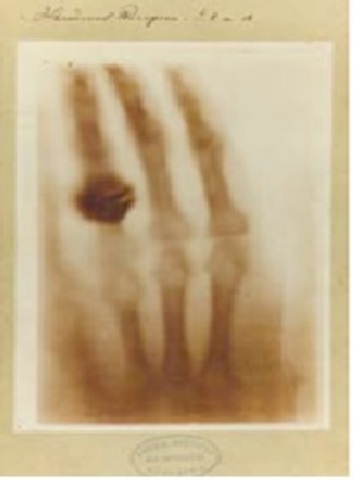

• Wilhelm Conrad Röntgen (1845-1923).

Wilhelm Conrad Röntgen (1845-1923).

descubrió el origen de estas técnicas,que permitieron el inicio del estudio de la Anatomía en el individuo vivo, surgió en 1896 cuando se realizó la primera radiografía de la mano humana.